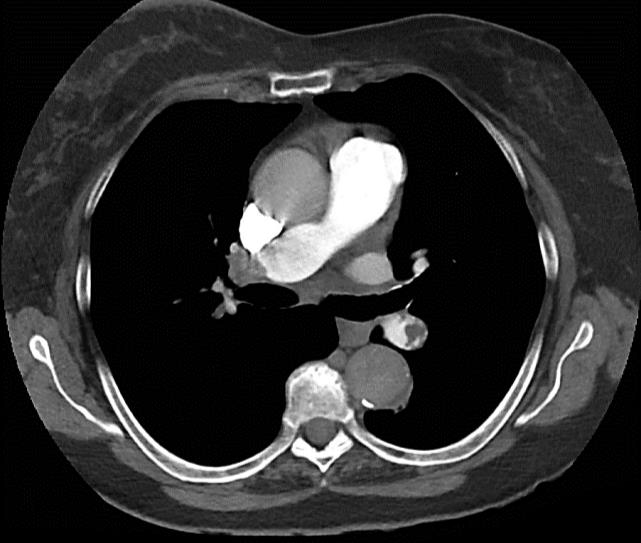

Mulher, 40 anos, em anticoagulação ambulatorial por trombose venosa profunda em membro inferior esquerdo com rivaroxabana 20mg uma vez ao dia, há um mês. Possui antecedentes de hipertensão arterial bem controlada com anlodipino 10 mg uma vez ao dia, obesidade e tabagismo (carga tabágica 20 maços/ano). Procura pronto socorro devido queixa de discreto desconforto respiratório há cerca de um dia. Optado por realizar angiotomografia de tórax (Figura 5). Nega quaisquer outras queixas e o exame físico não demonstra alterações, exceto edema estável do membro inferior esquerdo. Quando questionada a fundo, relata ser mãe de um filho saudável, mas que já apresentou dois abortos prévios. Além disso, conta ser esta a segunda trombose venosa, mas a última ocorreu na perna oposta há dois anos, quando usou varfarina por três meses e recebeu alta.

---------------------------------------------------------------Figura 5. Angiotomografia de tórax

Assinale a alternativa que apresenta qual a melhor opção de anticoagulação para esta paciente.